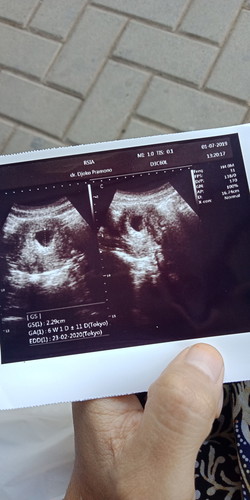

usg

Siang bunda, Maav mau tanya lg nie Pas malam sabtu akubdi usg, vonis dokter katanya janin nya udah meninggal, Tpi tadi di usg lg dengam dokter yg beda, tapi si janin masih ada, Mnrut bunda gmna ya?